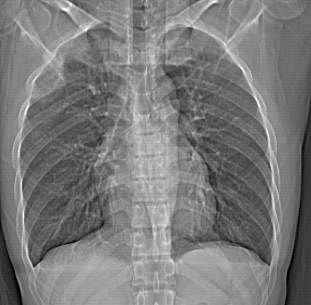

标题: CT12379:男,34岁,肺部病变,请求会诊! [打印本页]

标题: CT12379:男,34岁,肺部病变,请求会诊!

男,34岁,咳嗽2~3个月,无咳血,病初有发热。

两上肺磨玻璃样改变,均位于肺外周,考虑1、肺泡蛋白沉着症?2、肺泡炎?请询问有无养鸟史 3、脱屑性间质性肺炎?建议进一步检查、复查随访

两上肺的ggo,靠近胸膜,不是以节段分布,青年男性,个人意见为吸入性的真菌感染可能为大------------呼吸内科医生

两肺上叶近胸膜磨玻璃样阴影,考虑1、炎性病变。 。2、过敏性炎症?

再仔细阅读该病人的ct片,我们不难发现,病例所表现的正是外围型的肺泡蛋白沉积症表现,即:为多发性条片状、斑片状及斑块状高密度影,弥散、对称或不对称分布于两肺或一侧肺外围部位。病变区与正常肺组织及脏层胸膜面分界清晰,呈地图样改变。